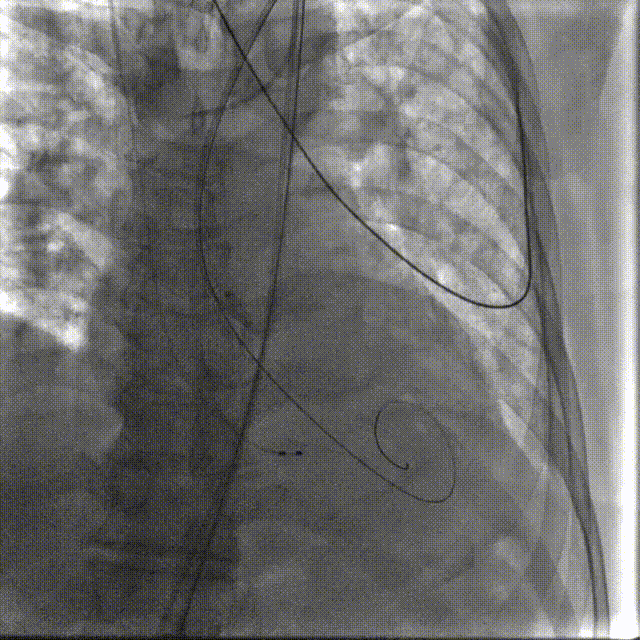

TaurusElite AV26瓣膜轻松过弓跨瓣,瓣膜初始定位瓣环0位,120bpm起搏下精准释放,释放到工作位后造影显示锚定充足,位置良好,冠脉未见遮挡,继续完成释放。

瓣膜初始定位

瓣膜释放过程